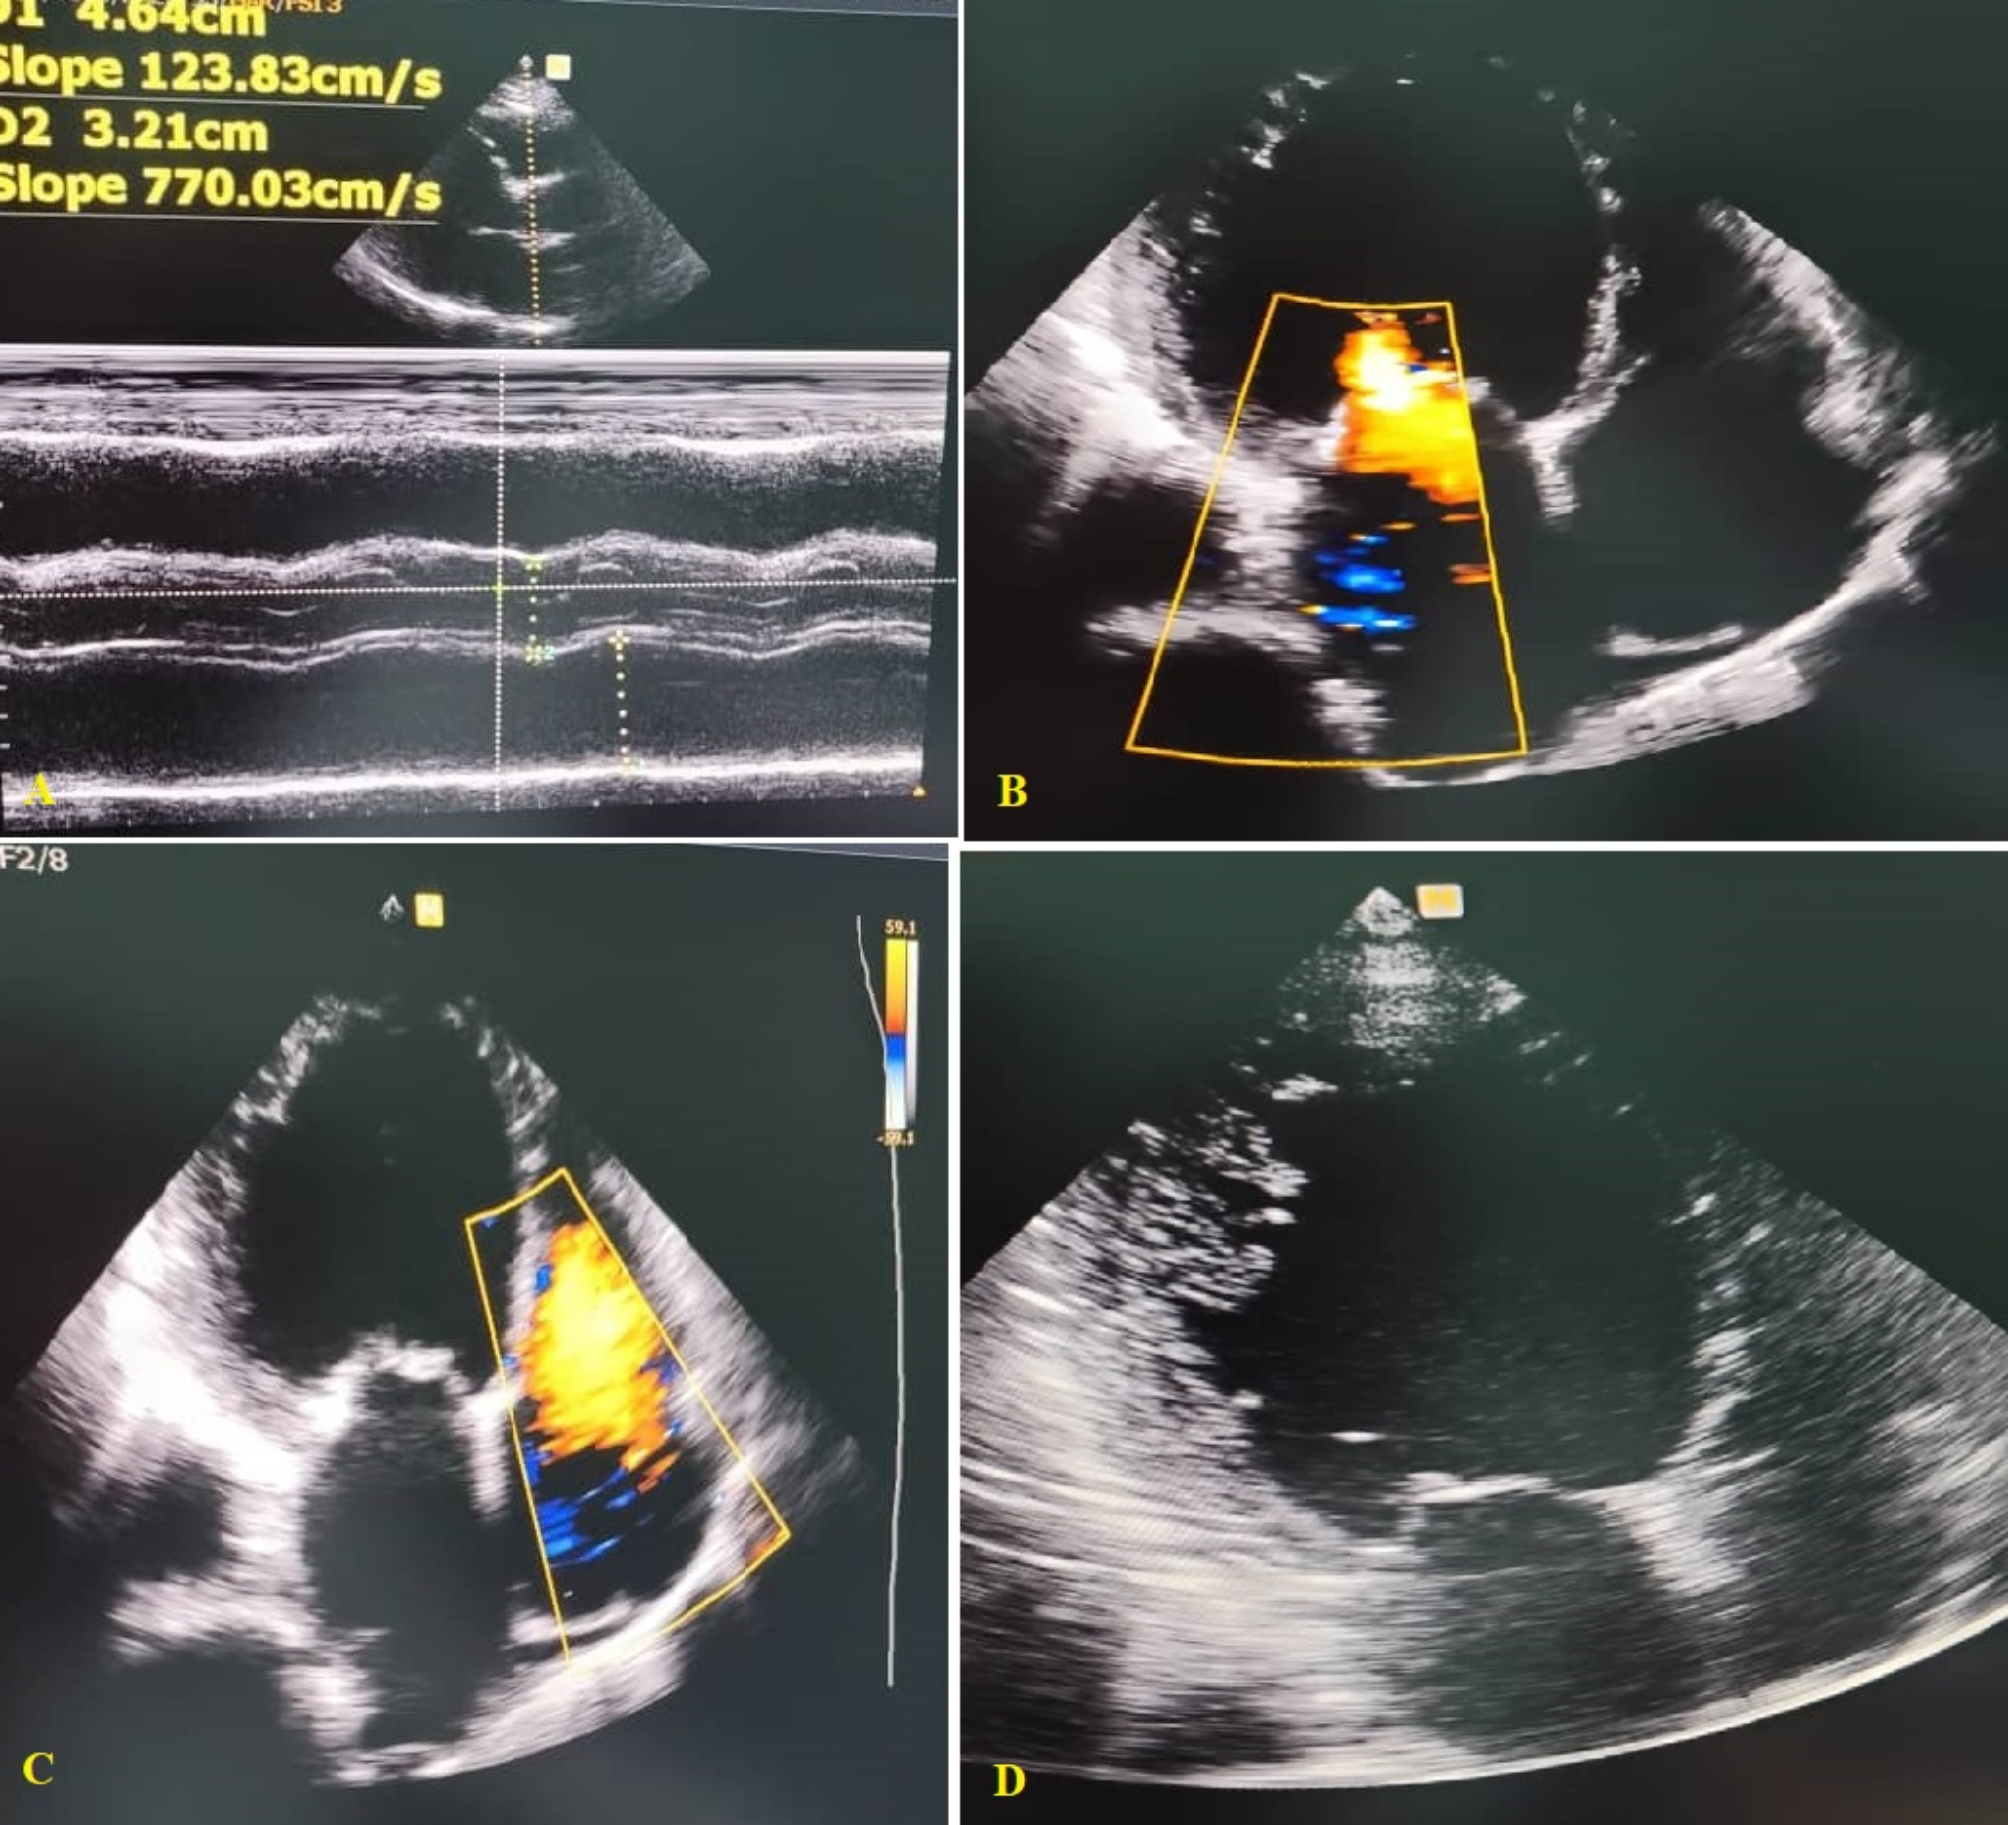

Fig. 1

Echocardiographic aspects of dilated cardiomyopathy. (A): Parasternal long-axis view: dilated left atrium and left ventricle in diastole. (B): Apical 4 chamber view: dilated left ventricle, dilated left atrium, significant secondary mitral regurgitation flow with Coanda effect. (C): Apical 4 chamber view: dilated cardiomyopathy with tricuspid regurgitation flow. (D): Apical 4 chamber view: global hypokinesia suggesting ischemic dilated cardiomyopathy.